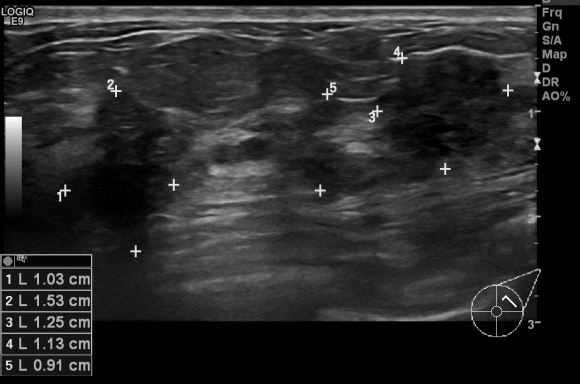

상기환자 40대 여성분으로 우측 겨드랑이 통증으로 내원하시여 유방 초음파 시행 후

좌측 1:00 ~2:00 시 방향에서 의심되는 멍울 조직검사 시행하여 좌측 침윤성 유관암

진단되었습니다.